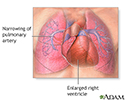

Primary pulmonary hypertension - illustration

Primary pulmonary hypertension

illustration

When the small arteries (blood vessels) of the lungs become narrowed, they cannot carry as much blood. When this happens, pressure builds up. This is called pulmonary hypertension.

The heart needs to work harder to force the blood through the vessels against this pressure. Over time, this causes the right side of the heart to become larger and malfunction. This condition is called right-sided heart failure, or cor pulmonale.